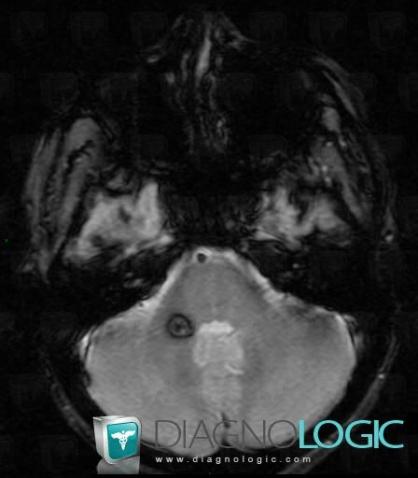

Cavernous angioma, Brainstem, MRI

Here is the specific information in the key image above:

- Diagnosis Cavernous angioma, Location(s) Brainstem, with gamuts

- Diagnosis Cavernous angioma, Location(s) Brainstem, with gamuts Brainstem lesion, Brainstem Hypointense T2WI or FLAIR lesion